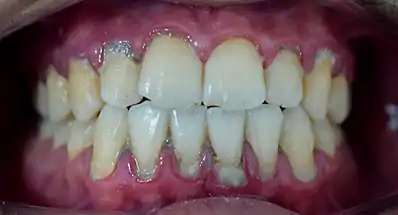

تشير التغيرات في اللون، وخاصةً زيادة الاحمرار، جنبًا إلى جنب مع التورم والميل المتزايد للنزيف، إلى التهاب قد يكون بسبب تراكم البلاك البكتيري بشكل عام، يعكس المظهر السريري للأنسجة الأنسجة الأساسية، سواء في الصحة أو المرض. عندما تكون أنسجة اللثة غير صحية، يمكن أن توفر بوابة لأمراض اللثة للتقدم إلى الأنسجة العميقة من اللثة، مما يؤدي إلى سوء تشخيص للاحتفاظ بالأسنان على المدى الطويل. يعتمد كل من نوع العلاج اللثوي وتعليمات الرعاية المنزلية المقدمة للمرضى من قبل أخصائيي الأسنان والرعاية الإصلاحية على الظروف السريرية للأنسجة.[3]

الأهمية السريرية

النظام البيئي الدقيق في تجويف اللثة، تغذيه دائماً بقايا الطعام واللعاب، وذلك بالتأكيد يدعم نمو العديد من الكائنات الحية الدقيقة، والتي يمكن أن تكون بعض ضار بالصحة. وبالتالي، يمكن أن تؤدي نظافة الفم غير السليمة أو غير الكافية إلى العديد من اضطرابات اللثة، بما في ذلك التهاب اللثة أو التهاب دواعم السن، والتي تعد من الأسباب الرئيسية لفشل الأسنان. أظهرت الدراسات الحديثة أيضًا أن الستيرويدات الابتنائية مرتبطة ارتباطًا وثيقًا بتضخم اللثة الذي يتطلب استئصال اللثة في كثير من الحالات. يحدث تراجع اللثة عندما تكون هناك حركة قمية لهامش اللثة بعيدًا عن سطح العض (الإطباق).[6] قد يشير إلى التهاب أساسي مثل التهاب دواعم السن [7] أو تقيح، [7] تشكل الجيب، جفاف الفم [7] أو إزاحة اللثة الهامشية بعيدًا عن السن بواسطة ميكانيكي (مثل الفرشاة)، [7] كيميائي، أو الوسائل الجراحية.[8] قد يؤدي تراجع اللثة، بدوره، إلى تعريض رقبة الأسنان وتركها عرضة لتأثير المحفزات الخارجية، وقد يسبب حساسية للجذر.[7]

الأمراض اللِّـثَـوِية

يستضيف فم الإنسان حتى في الحالة الصحية مئات من البكتيريا والأحياء الدقيقة، تؤلف تلك الأحياء مع بعضها ومع مضيفها منظومة احيائية صغرية، الطاقة اللازمة لهذه المنظومة تتاتى من اللعاب والمواد الغذائية الداخلة عبر الفم. طالما أن هناك حالة توازن بين نشاط البكتيريا الممرضة وتلك غير الممرضة بالإضافة للعوامل المناعية للمضيف فلا وجود للمرض اللثوي أو الداعم. ولكن في الحالات التي يحدث فيها خلل في هذا التوازن الدقيق تبدأ لدينا الإصابة المرضية. معظم الجراثيم اللِّـثَـوِية الممرضة هي جراثيم لا هوائية وسالبة الغرام، وأشهرها :